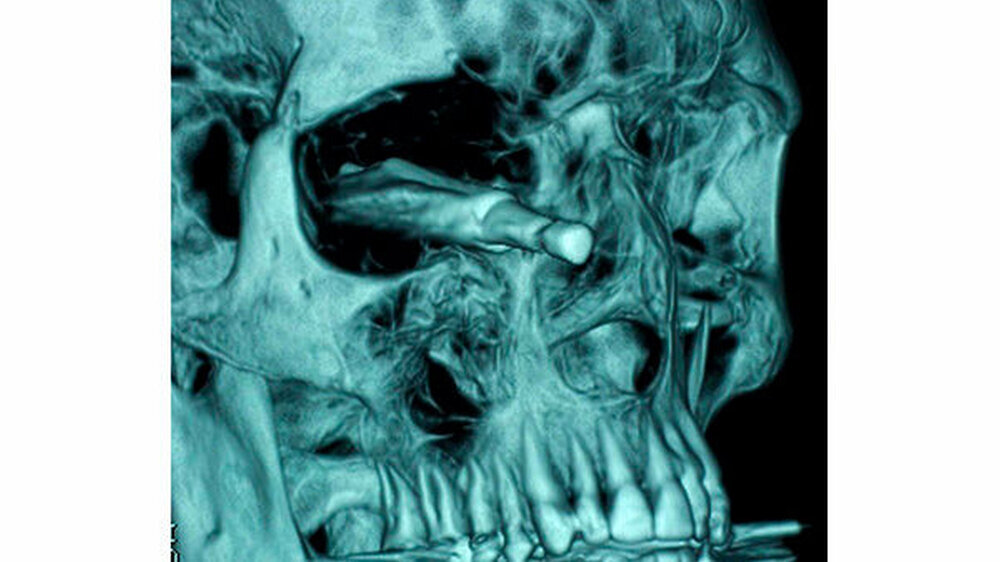

Fremdkörper im Gesicht

Vom Bohrer im Kopf bis zum Schlüssel in der Kieferhöhle: Die MKG-Chirurgen der Charité haben ausgewählte Patientenfälle mit Fremdkörpern im Gesicht zusammengestellt. In unserer Fotostrecke finden Sie die eindrucksvollen Aufnahmen.